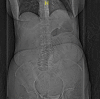

Paraduodenal hernias are congenital internal hernias that usually present with non-specific symptoms, and are therefore rarely diagnosed preoperatively. Left-sided paraduodenal hernias are three times more likely to occur than right-sided ones. Both hernias present similarly, but have a differing embryological basis. Here, the case of a 76-year-old woman with a left paraduodenal hernia presenting with small bowel obstruction is presented, and a brief discussion of the literature on its diagnosis and management given.